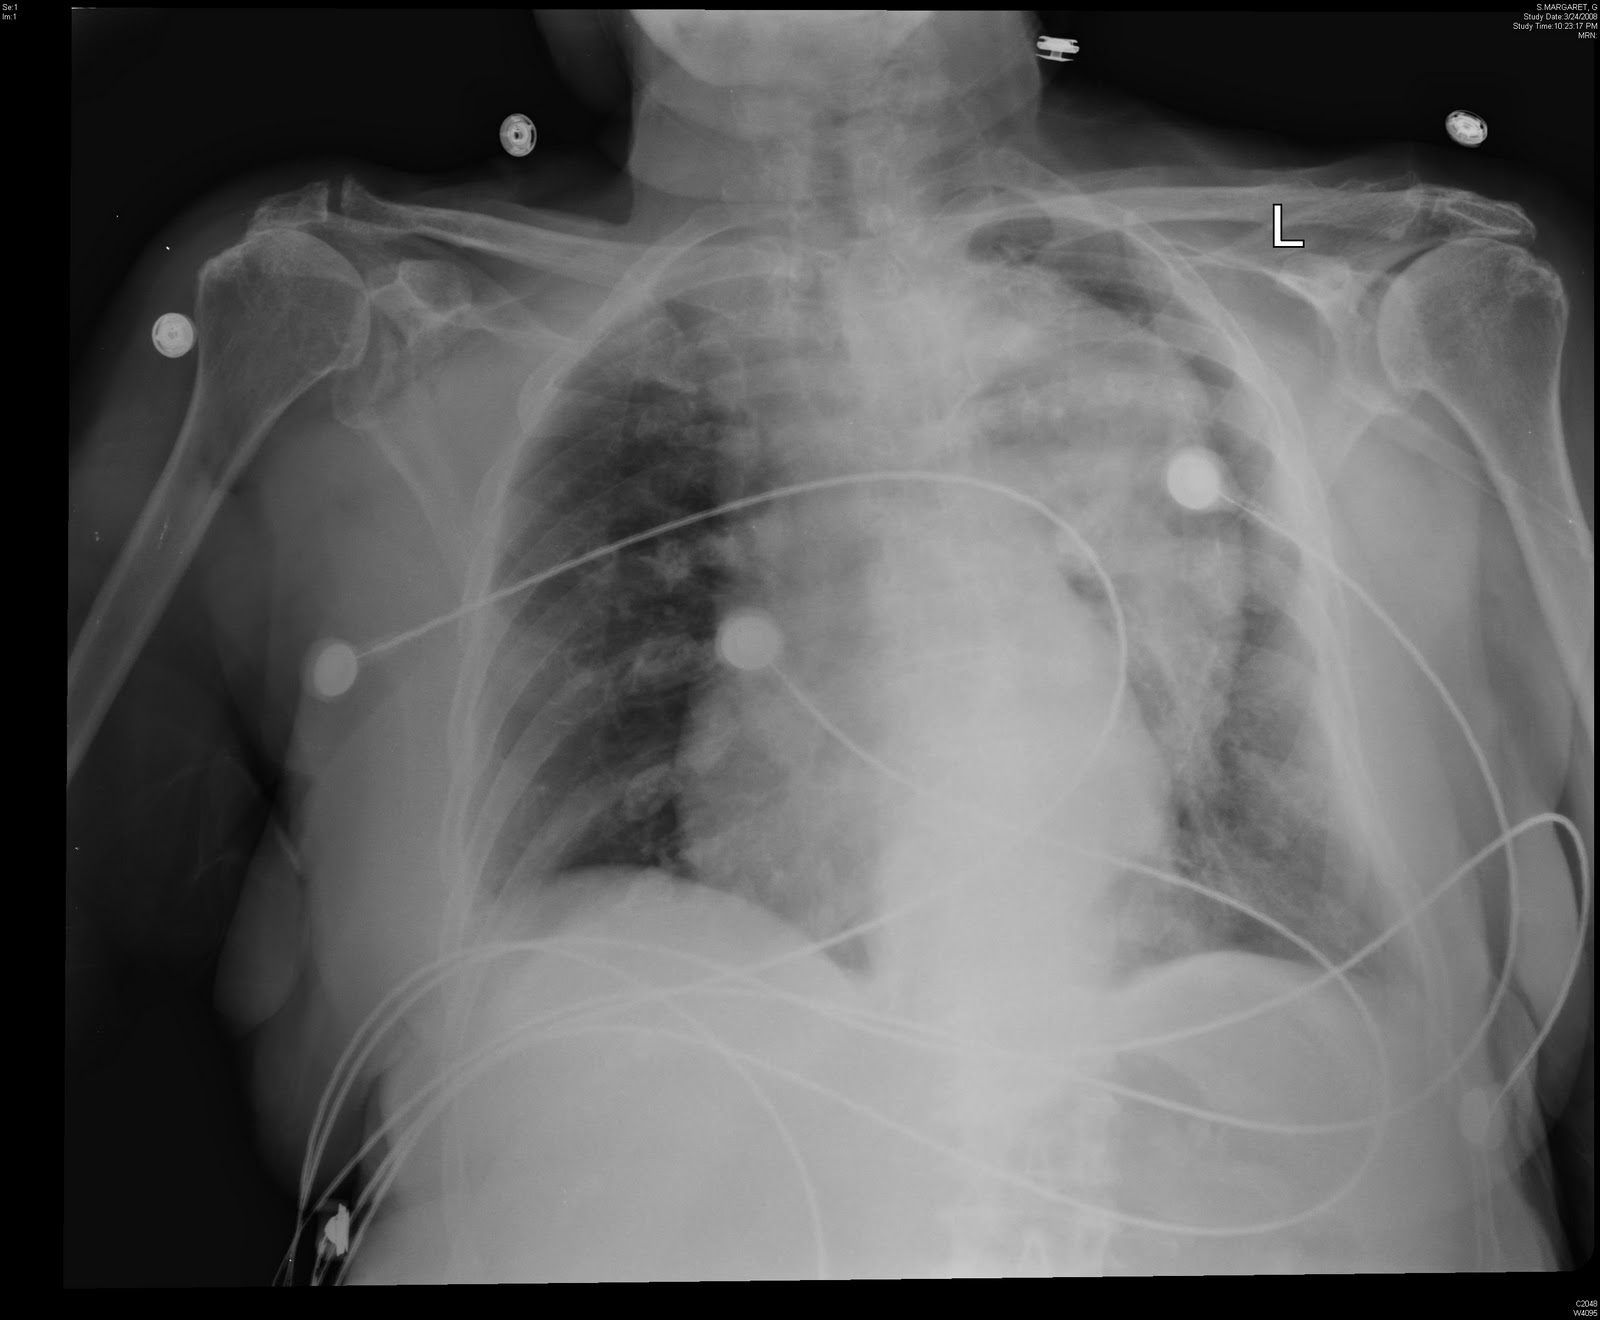

Aortic Dissection Without Mediastinal Haemorrhage CXR 1 Flickr

https://c2.staticflickr.com/4/3453/3742801148_e431336c9e_b.jpg